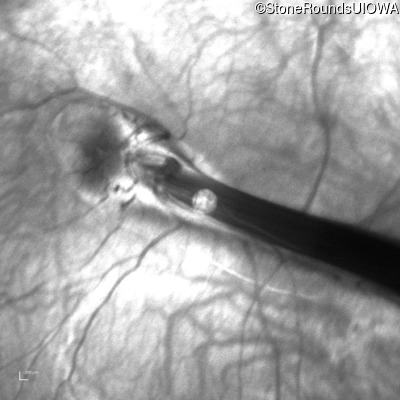

AD Familial Exudative Vitreoretinopathy (IIIE2b)

Age at visit: 23 months

This 23 month old male has had nystagmus since shortly after birth. He was born at term (7lbs 12oz).